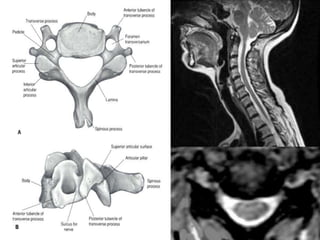

Note:the black line directly posterior to the vertebral bodies and relative

Thinning of spinal cord, note normal disc height

Mid-sagittal diameter: width

1:5 ratio leads to necrosis of gray

matter

• Ogino H: Canal diameter, anteroposterior compression ratio

and spondylotic myelopathy of the cervical spine. Spine 1983;

8:1-15

• Cord compression causes ischemia and direct mechanical

trauma